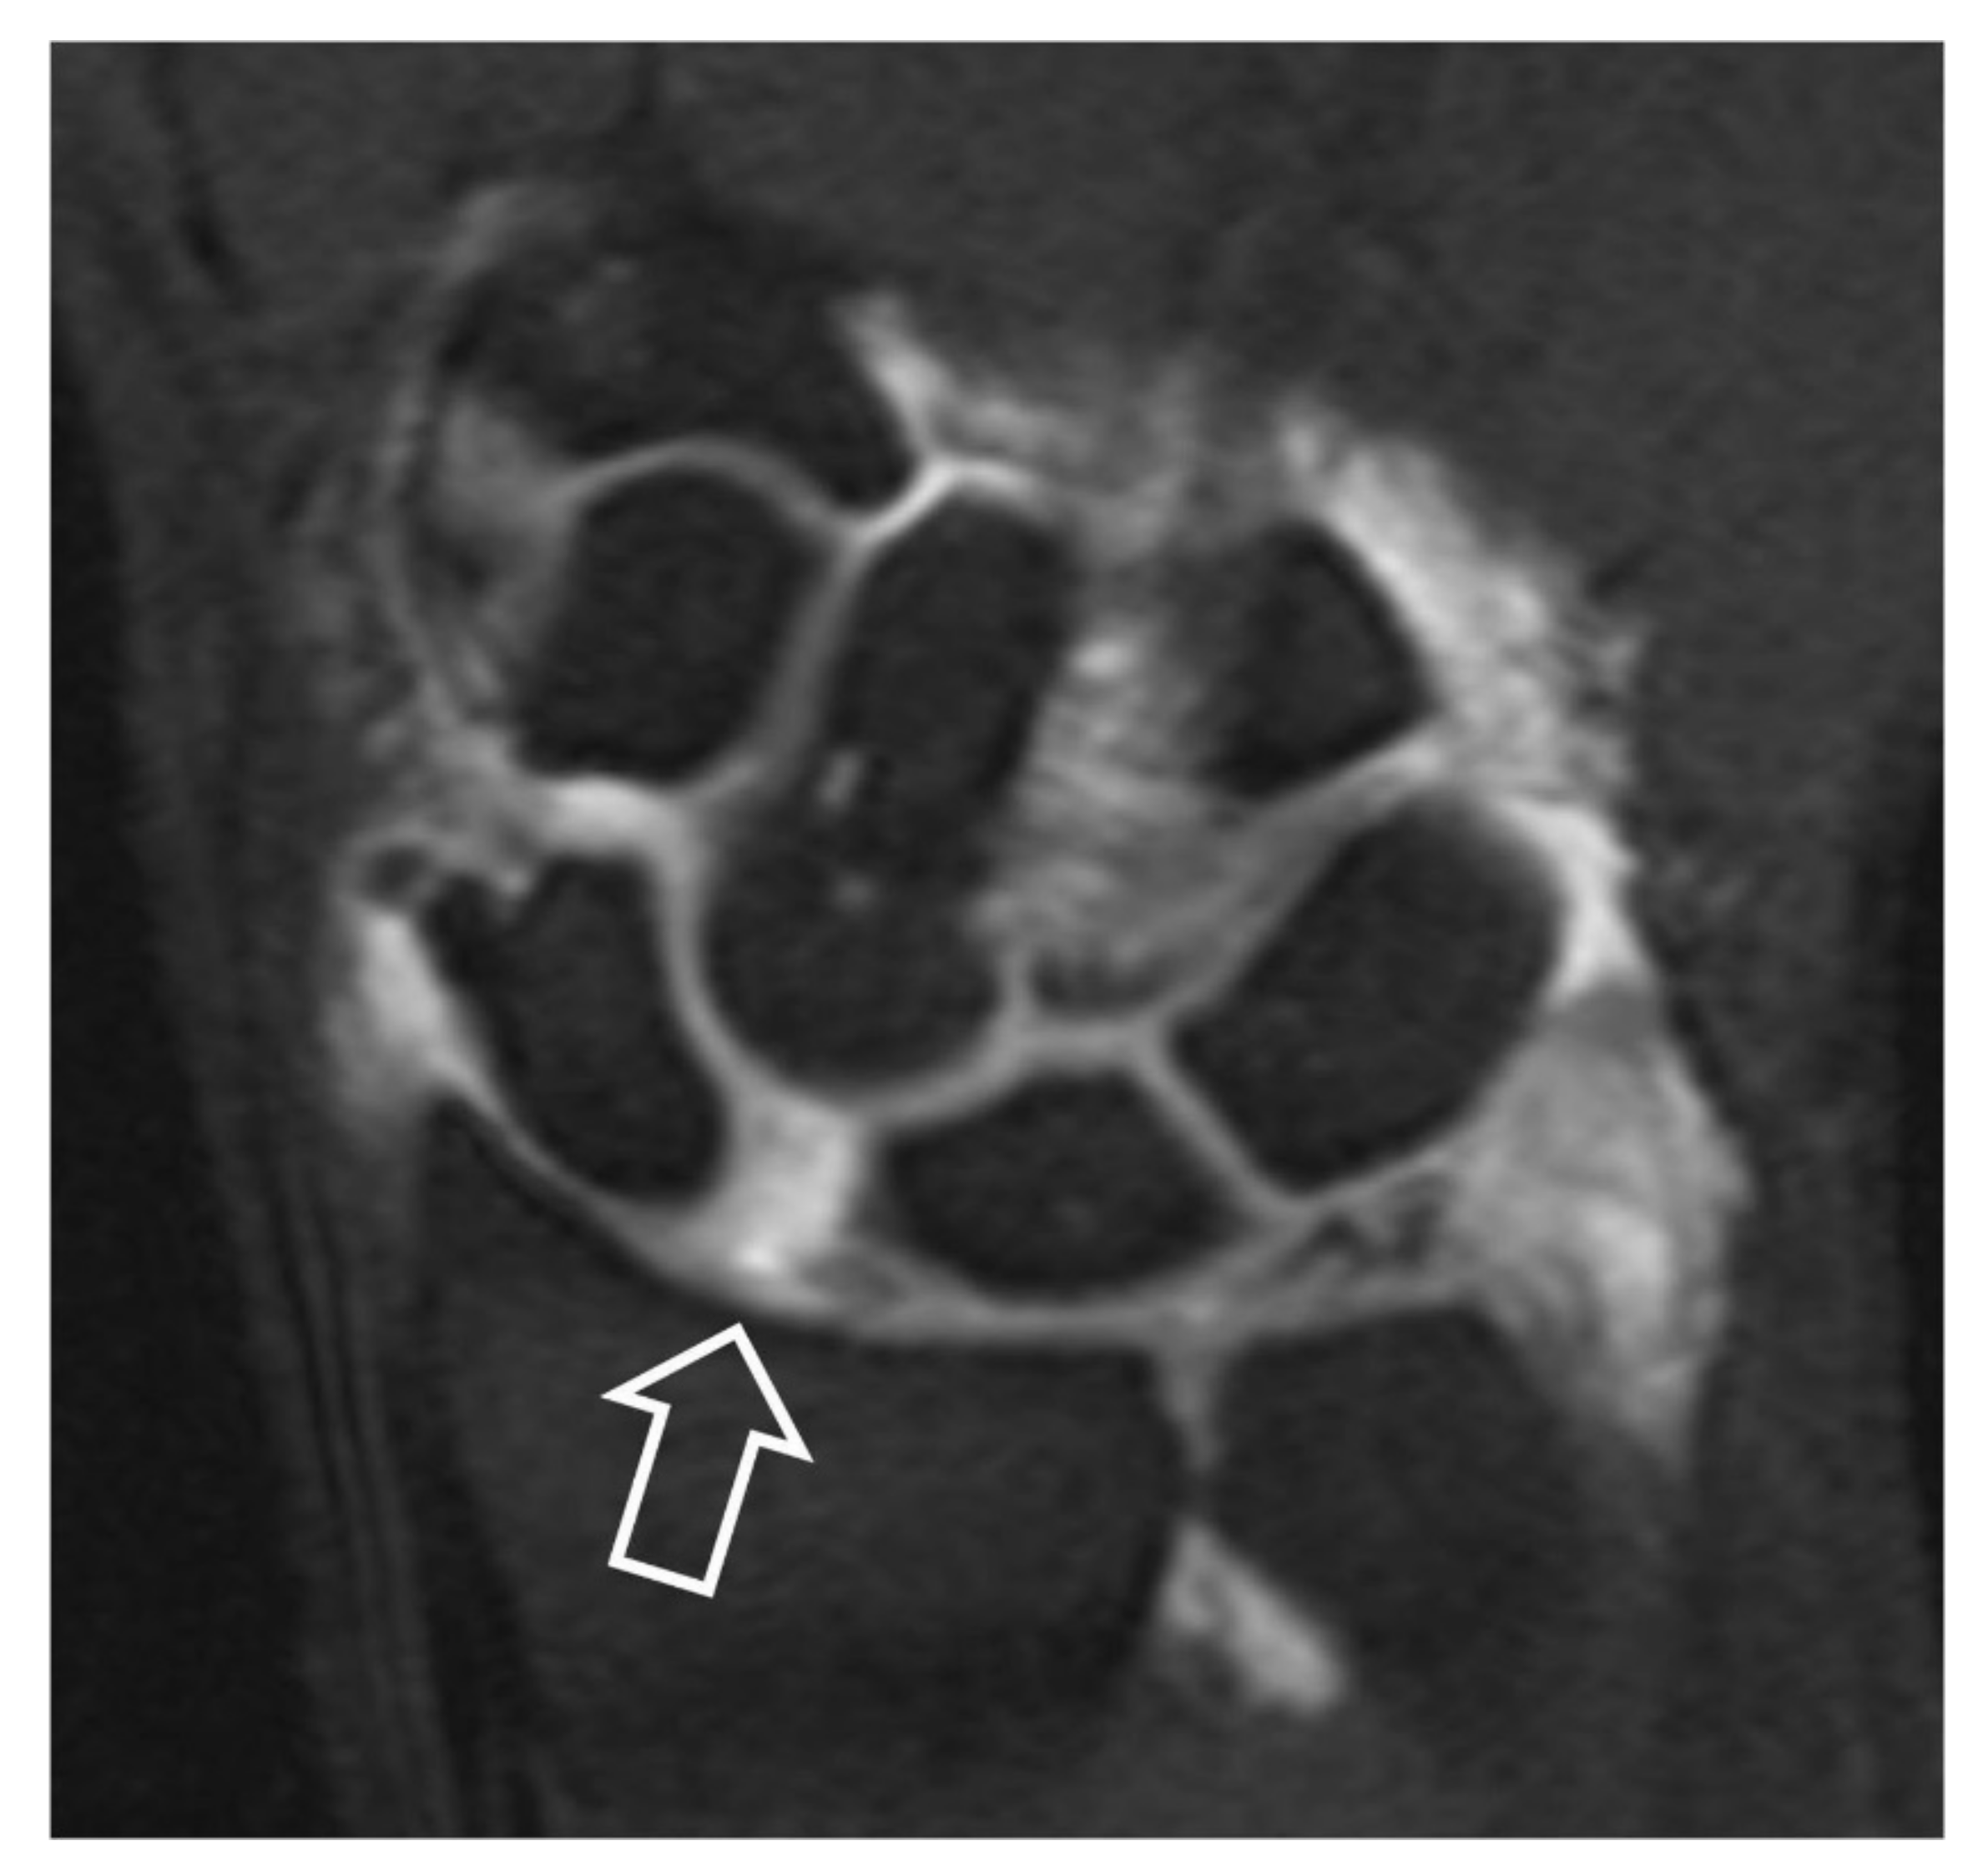

MRa can accurately assess the SLL disruption by depicting the absence of the ligament and the opacification of the midcarpal joints (Figure 12) [11]. Early changes of the articular cartilage in extreme detail concerning depth, height and thickness can be depicted (Figure 13) [12]. Axial images on MRI and MRa are more suitable for the estimation of wrist ligaments and sagittal images for the evaluation of scaphoid bone and DISI (Figure 14). Currently, MRI and MRa are the most widely preferred methods in diagnosing wrist pain [13]. Comparison of the various imaging modalities is shown in Table 3.

Figure 12.

Coronal fat suppressed T1w MR arthrographic image following a single injection in the radiocarpal joint. Scapholunate diastasis (open arrow) and opacification of the midcarpal joints suggest SLL disruption.